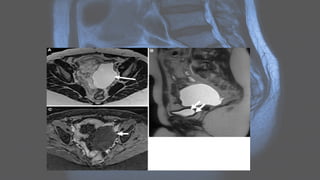

MRI

• May show an ill-defined adnexal mass containing fluid with various

signal intensities:

• T1: if there is proteinaceous debris in a dilated tube, then it may have

increased T1 signal

• T1+C (Gd): wall and surrounding tissues may enhance

Adenomyosis